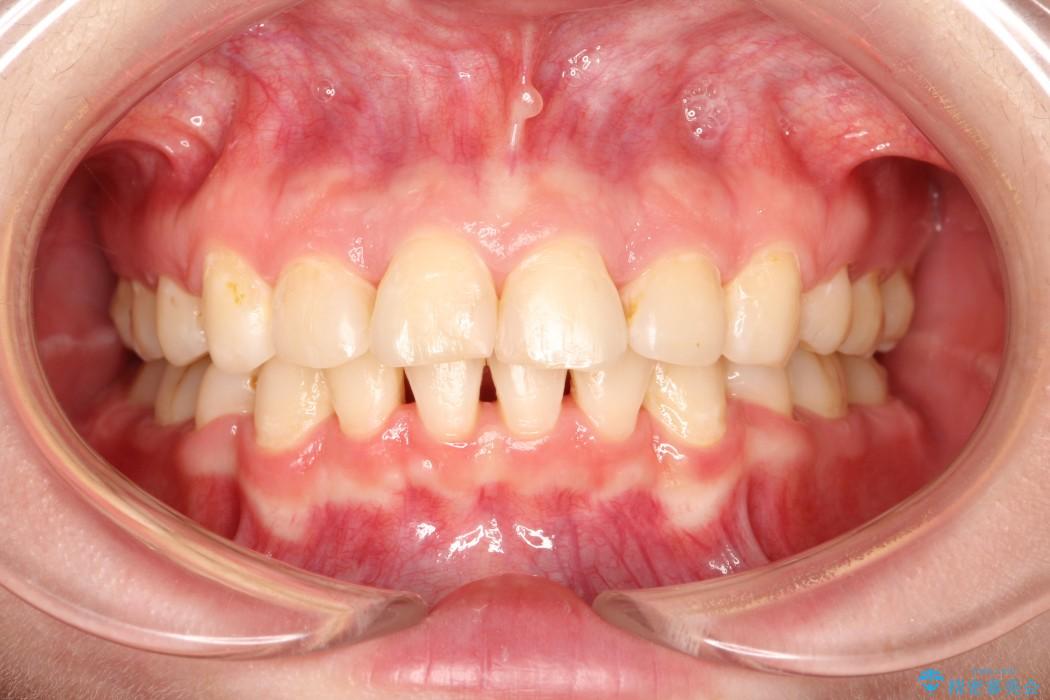

【20代女性】出っ歯の矯正 治療例

口元が出ていることを気にされて来院されました。

治療後について

出ている歯を引っ込めるためのスペースを作るため、上下左右の小臼歯を抜歯し、ワイヤー矯正を行いました。治療後は、口元がスッキリとしたことで患者様にも喜んでいいただきました。